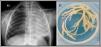

A boy aged 3 years presented with increased work of breathing in the context of febrile acute bronchitis. The salient findings of the physical examination were increased work of breathing with generalized retractions, tachypnoea with 70 bmp, bilateral expiratory wheezing with hypoventilation in the left hemithorax and an SaO2 of 84%. The plain chest radiograph showed complete opacification of the left hemithorax with tracheal shift toward the involved lung and hyperinflation of the contralateral lung, all of which was compatible with complete atelectasis of the left lung (Fig. 2A). A few hours later, a flexible bronchoscopy examination revealed mucus plugging in the left main bronchus occluding the entire bronchial lumen. Aspiration achieved full clearance of the plugging, with removal of bronchial casts (Fig. 2B), and full re-expansion of the left lung with rapid improvement of the respiratory symptoms. Testing of a bronchoalveolar lavage sample detected adenovirus, confirming the diagnosis of plastic bronchitis secondary to adenovirus infection, an association that is rare in our region.3,4 The patient was then discharged, at which time the physical examination was normal, and has since experienced recurrent episodes of mild bronchitis.

(A) Lung computed tomography scan: bilateral mosaic attenuation pattern compatible with bronchiolitis obliterans. (B) Flexible bronchoscopy: tracheal stenosis with reduction of 60% to 70% of the tracheal lumen due to granuloma. (C) Flexible bronchoscopy, 3 months after image B: residual membrane after steroid therapy and dilations.